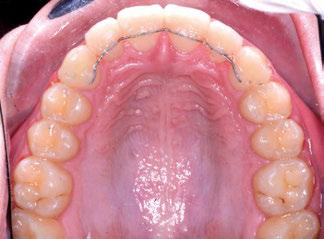

Tras la terminación de la fase ortopédica, se continuó con la colocación de los brackets

mencionados anteriormente. La prescripción de estos fue de alto torque en los incisivos superiores y en los cuatro caninos, y de bajo en los incisivos inferiores. Tras 12 meses desde la colocación de los brackets y una vez conseguida la normalización de las relaciones oclusales, se colocaron unos retenedores fijos de canino a canino en ambas arcadas de acero trenzado de 6 hilos (.017” superior y .019” inferior) y un guarda de contención nocturna hasta la terminación del crecimiento puberal.

Los retenedores fijos (13, 14) FLAS y FLAI (férula lingual anterosuperior e anteroinferior, respectivamente) de alambre de acero trenzado de 6 hilos, cementados de canino a canino, aportan estabilidad a los sectores anteriores, y el splint o guarda como aparato de contención nocturna hasta la terminación del crecimiento puberal, aporta estabilidad a los resultados conseguidos.